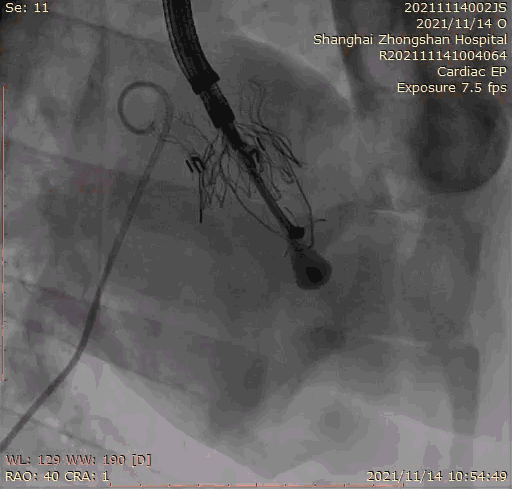

本次臨床前研究經(jīng)右側(cè)頸靜脈置入LuX-Valve Plus輸送系統(tǒng)可調(diào)彎鞘管,在DSA及超聲引導(dǎo)下將人工三尖瓣瓣膜植入到原有三尖瓣位置,利用獨特的錨定技術(shù)將人工瓣膜支架可靠固定在預(yù)定的位置。

上海中山醫(yī)院葛均波院士、錢菊英院長、周達新教授、潘文志教授、潘翠珍教授、李偉教授共同完成此次臨床前研究。術(shù)后葛均波院士對Lux-Valve Plus的器械操作性能給予了高度評價,DSA和超聲影像也顯示出在本次研究中Lux-Valve Plus的安全性和有效性俱佳。